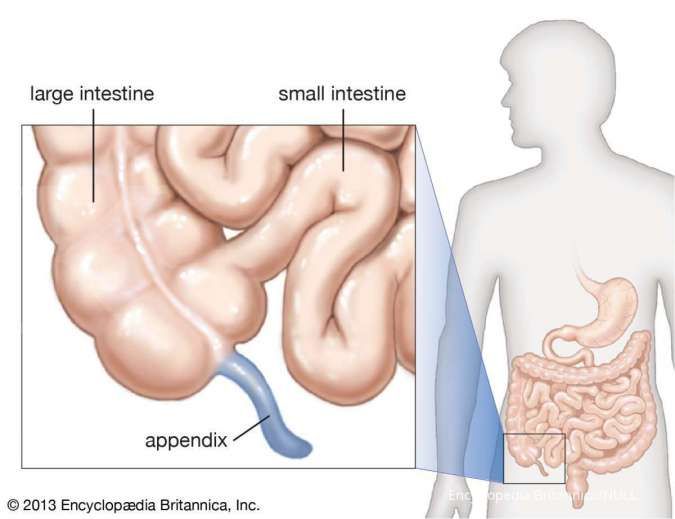

Cari Tahu Letak Dan Penyebab Usus Buntu

Cari Tahu Letak Dan Penyebab Usus Buntu